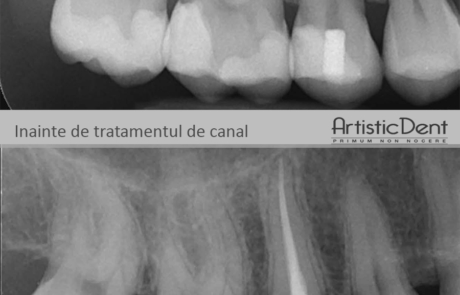

The images below will help you get an idea of what the canal treatment of an infected tooth is.